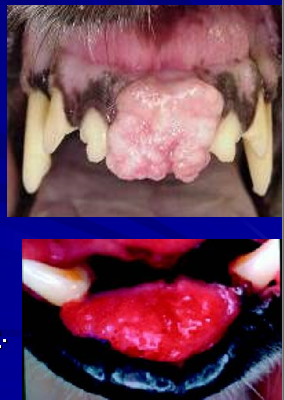

18

Q

What lesions are shown here?

A